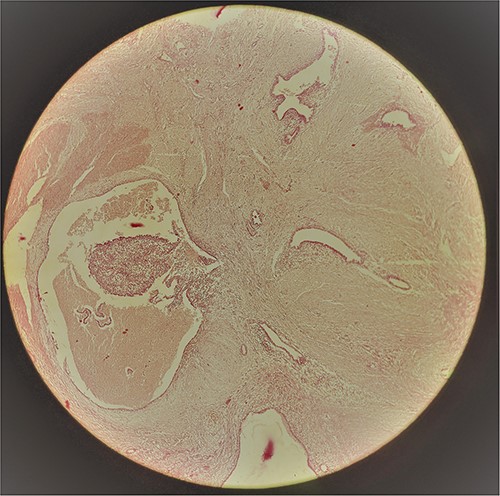

A 29-year-old female patient presented with a complaint of pain in lower abdomen for last 2 years. The pain would aggravate during menses. She also complained of a swelling at the site of her previous lower segment caesarean section (LSCS) scar for 1 year, which had gradually increased in size. She had underwent LSCS two and half years back. Nothing else was significant in history. Examination revealed a well circumscribed, firm mass at the surgical scar site, slightly to the right of the midline, ⁓6 cm × 5 cm in dimensions, fixed to underlying structures, especially on contraction of the rectus abdominis. Ultrasonography showed a heterogenous mass in the relation to the scar. Magnetic resonance imaging (MRI) revealed a well-defined heterogenous lesion extending into right rectus abdominus muscle, 4.2*3.1*2.2 cm in size with multiple thin septations within it, suggestive of scar endometriosis. Intraoperatively an irregular mass lesion was found in the subcutaneous scar tissue and was noted to be invading the rectus abdominis (Fig. 1). Enbloc excision of the endometrioma along with the involved portion of rectus sheath and rectus abdominis muscle was done (Figs 2 and 3). In view of potential tension on the fascial closure onlay mesh reinforcement was also done. The post operative course was uneventful and the patient was discharged on 7th post operative day. The histopathological examination confirmed the presence of endometrial tissue within the excised mass with skeletal muscle bundles infiltrated by endometrial glands (Fig. 3). Patient is on regular follow up and is recurrence free at 9 months.

Anterior aspect of the endometrioma (pointed out by the arrow) delineated after dissection of skin flap.